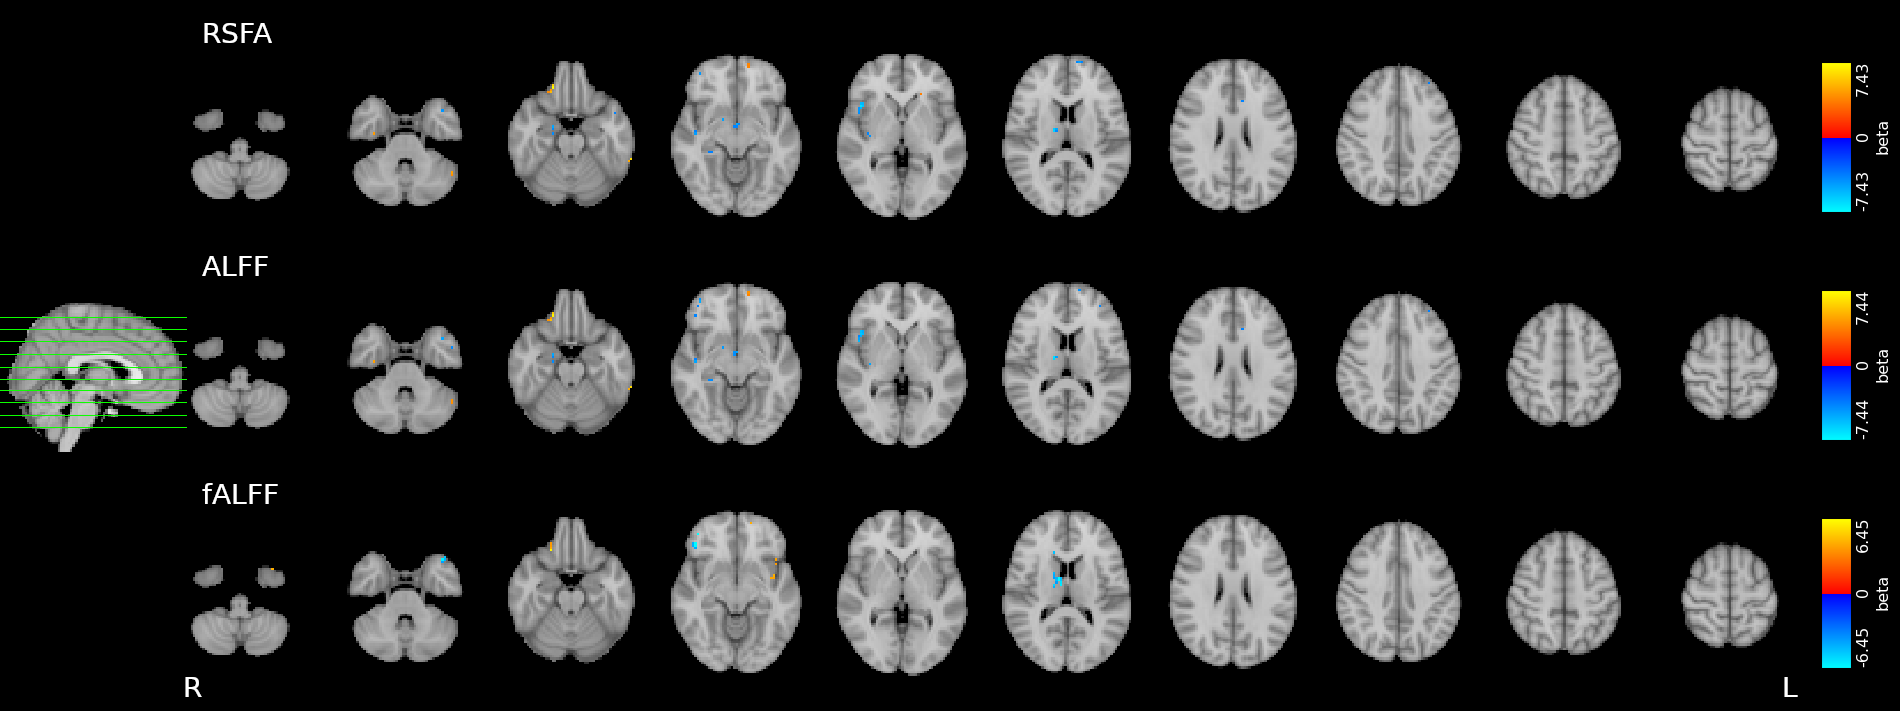

Results: CVR, RSF, and tasks

Motor task

Simon task, congruent responses

Simon task, incongruent responses

The relationship between CVR, RS fluctuations, and tIA

might be highly subject specific

or absent altogether.

Take home message #3

- We did not observe a statistically significant effect of CVR on RS fluctuations, or of CVR and RS fluctuations on task induced activity, most probably due to the high variability between subjects

-

The failure of generalisation of previous observations might be related to different methods, but whether this is related to a better denoising and signal quality or to a possibly non optimal setting (e.g. compared to gas challenges) is uncertain

-

A different statistical perspective (i.e. Bayesian) is required to exclude any relationship between CVR and RS fluctuations, and further analyses are required to improve the agreement between CVR and RS fluctuations

-